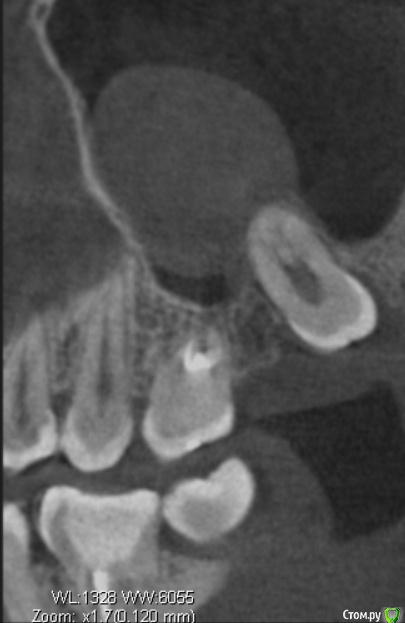

Bier Опубликовано 14 марта, 2017 Поделиться Опубликовано 14 марта, 2017 чтобы говорить о необходимости РВК - надо видеть нормальный снимок 26 зуба. Он не попадает в срез КТ на вашем скриншоте.Я бы ограничился удалением 28 зуба.С 26 - нужны доп снимки. 1 Ссылка на комментарий

tineola Опубликовано 15 марта, 2017 Автор Поделиться Опубликовано 15 марта, 2017 (изменено) Сделала несколько скриншотов, прикрепляю к сообщению. Надеюсь, это то, что нужно.Может у кого-то из врачей будет время и возможность посмотреть КТ (ссылка в первом сообщении поста). Получила результаты гистологии первой кисты пазухи, которая год назад была удалена:Микроописание: Присланный материал представлен фрагментом полипозно-отечной слизистой оболочки, с концевым отделами слизисто-серозных желез. Эпителий слущен, гиалиоз базальных мембран, строма резко отечна, с диффузной лимфоцитарно-лейкоцитарной инфильтрацией. Патзаключение: хронический воспалительный процесс. Изменено 15 марта, 2017 пользователем tineola Ссылка на комментарий

tineola Опубликовано 15 марта, 2017 Автор Поделиться Опубликовано 15 марта, 2017 Еще скриншоты. Другая проекция из КТ. Ссылка на комментарий